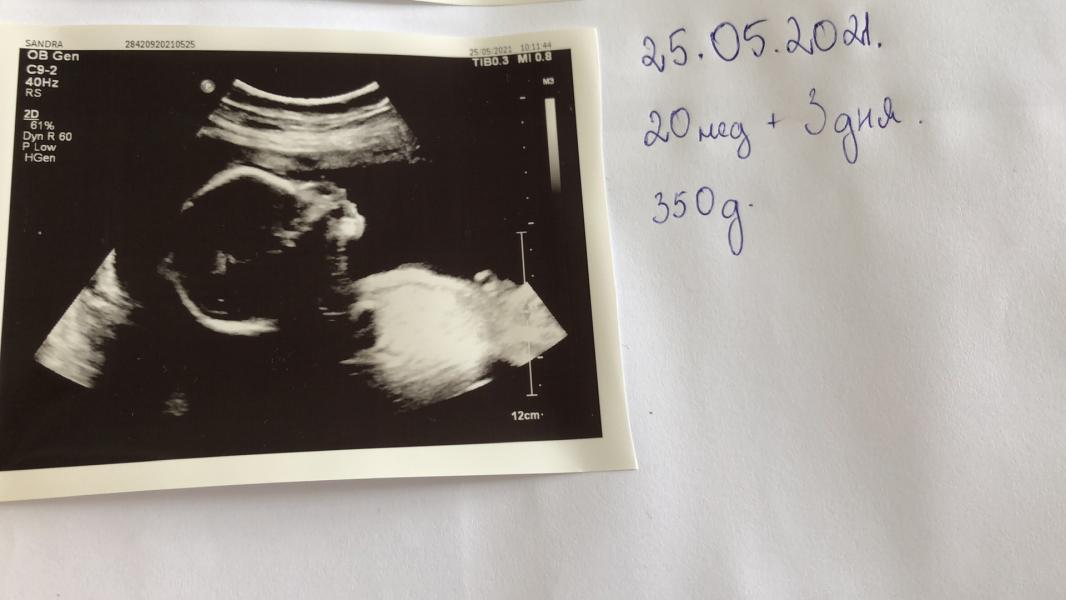

П.С. Девочка весит 350 граммов и здоровенькая все работает как надо, но вот эта киста не ноги напрягла.